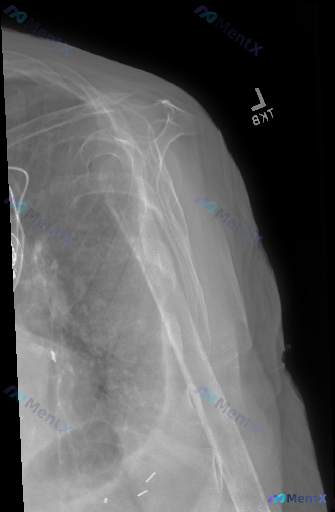

- 肱骨近端到肱骨干有明显骨折,多发碎骨块,断端移位重叠很显著,肱骨头解剖结构模糊,盂肱关节正常对位已经破坏

- 肩胛骨、锁骨远端(可见部分)、影像内肋骨看起来没有明显骨折脱位

- 肱骨近端和腋下周围软组织肿胀明显,密度增高

- 影像底部有多枚高密度金属异物影,像是缝合锚钉或固定材料